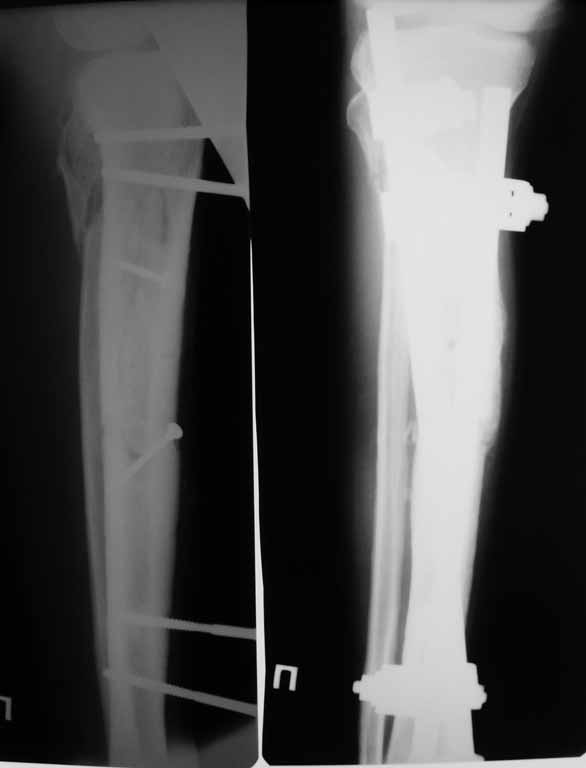

Привожу пример: Пациент с открытой тяжелой ЧМТ.

Диагноз при поступлении: Открытый оскольчатый перелом свода и основания черепа,субдуральная гематома, ушиб головного мозга тяжелой степени. Открытый оскольчатый перелом костей правой голени. Шок 3 Кома 3

При поступлении оперирован : трепанация, ПХО, остеосинтез голени.

Консолидация в аппарате внешней фиксации к 2 месяцам. Аппарат снят через 2,5 месяца.

Фото в приложении.